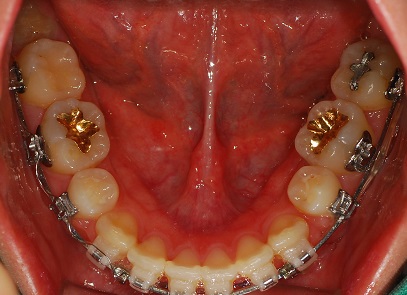

하악 사진

여기도 아주 조금 남은 공간이 보이시나요?

찾기 힘들정도로 조금 남앗어요ㅎㅎㅎ